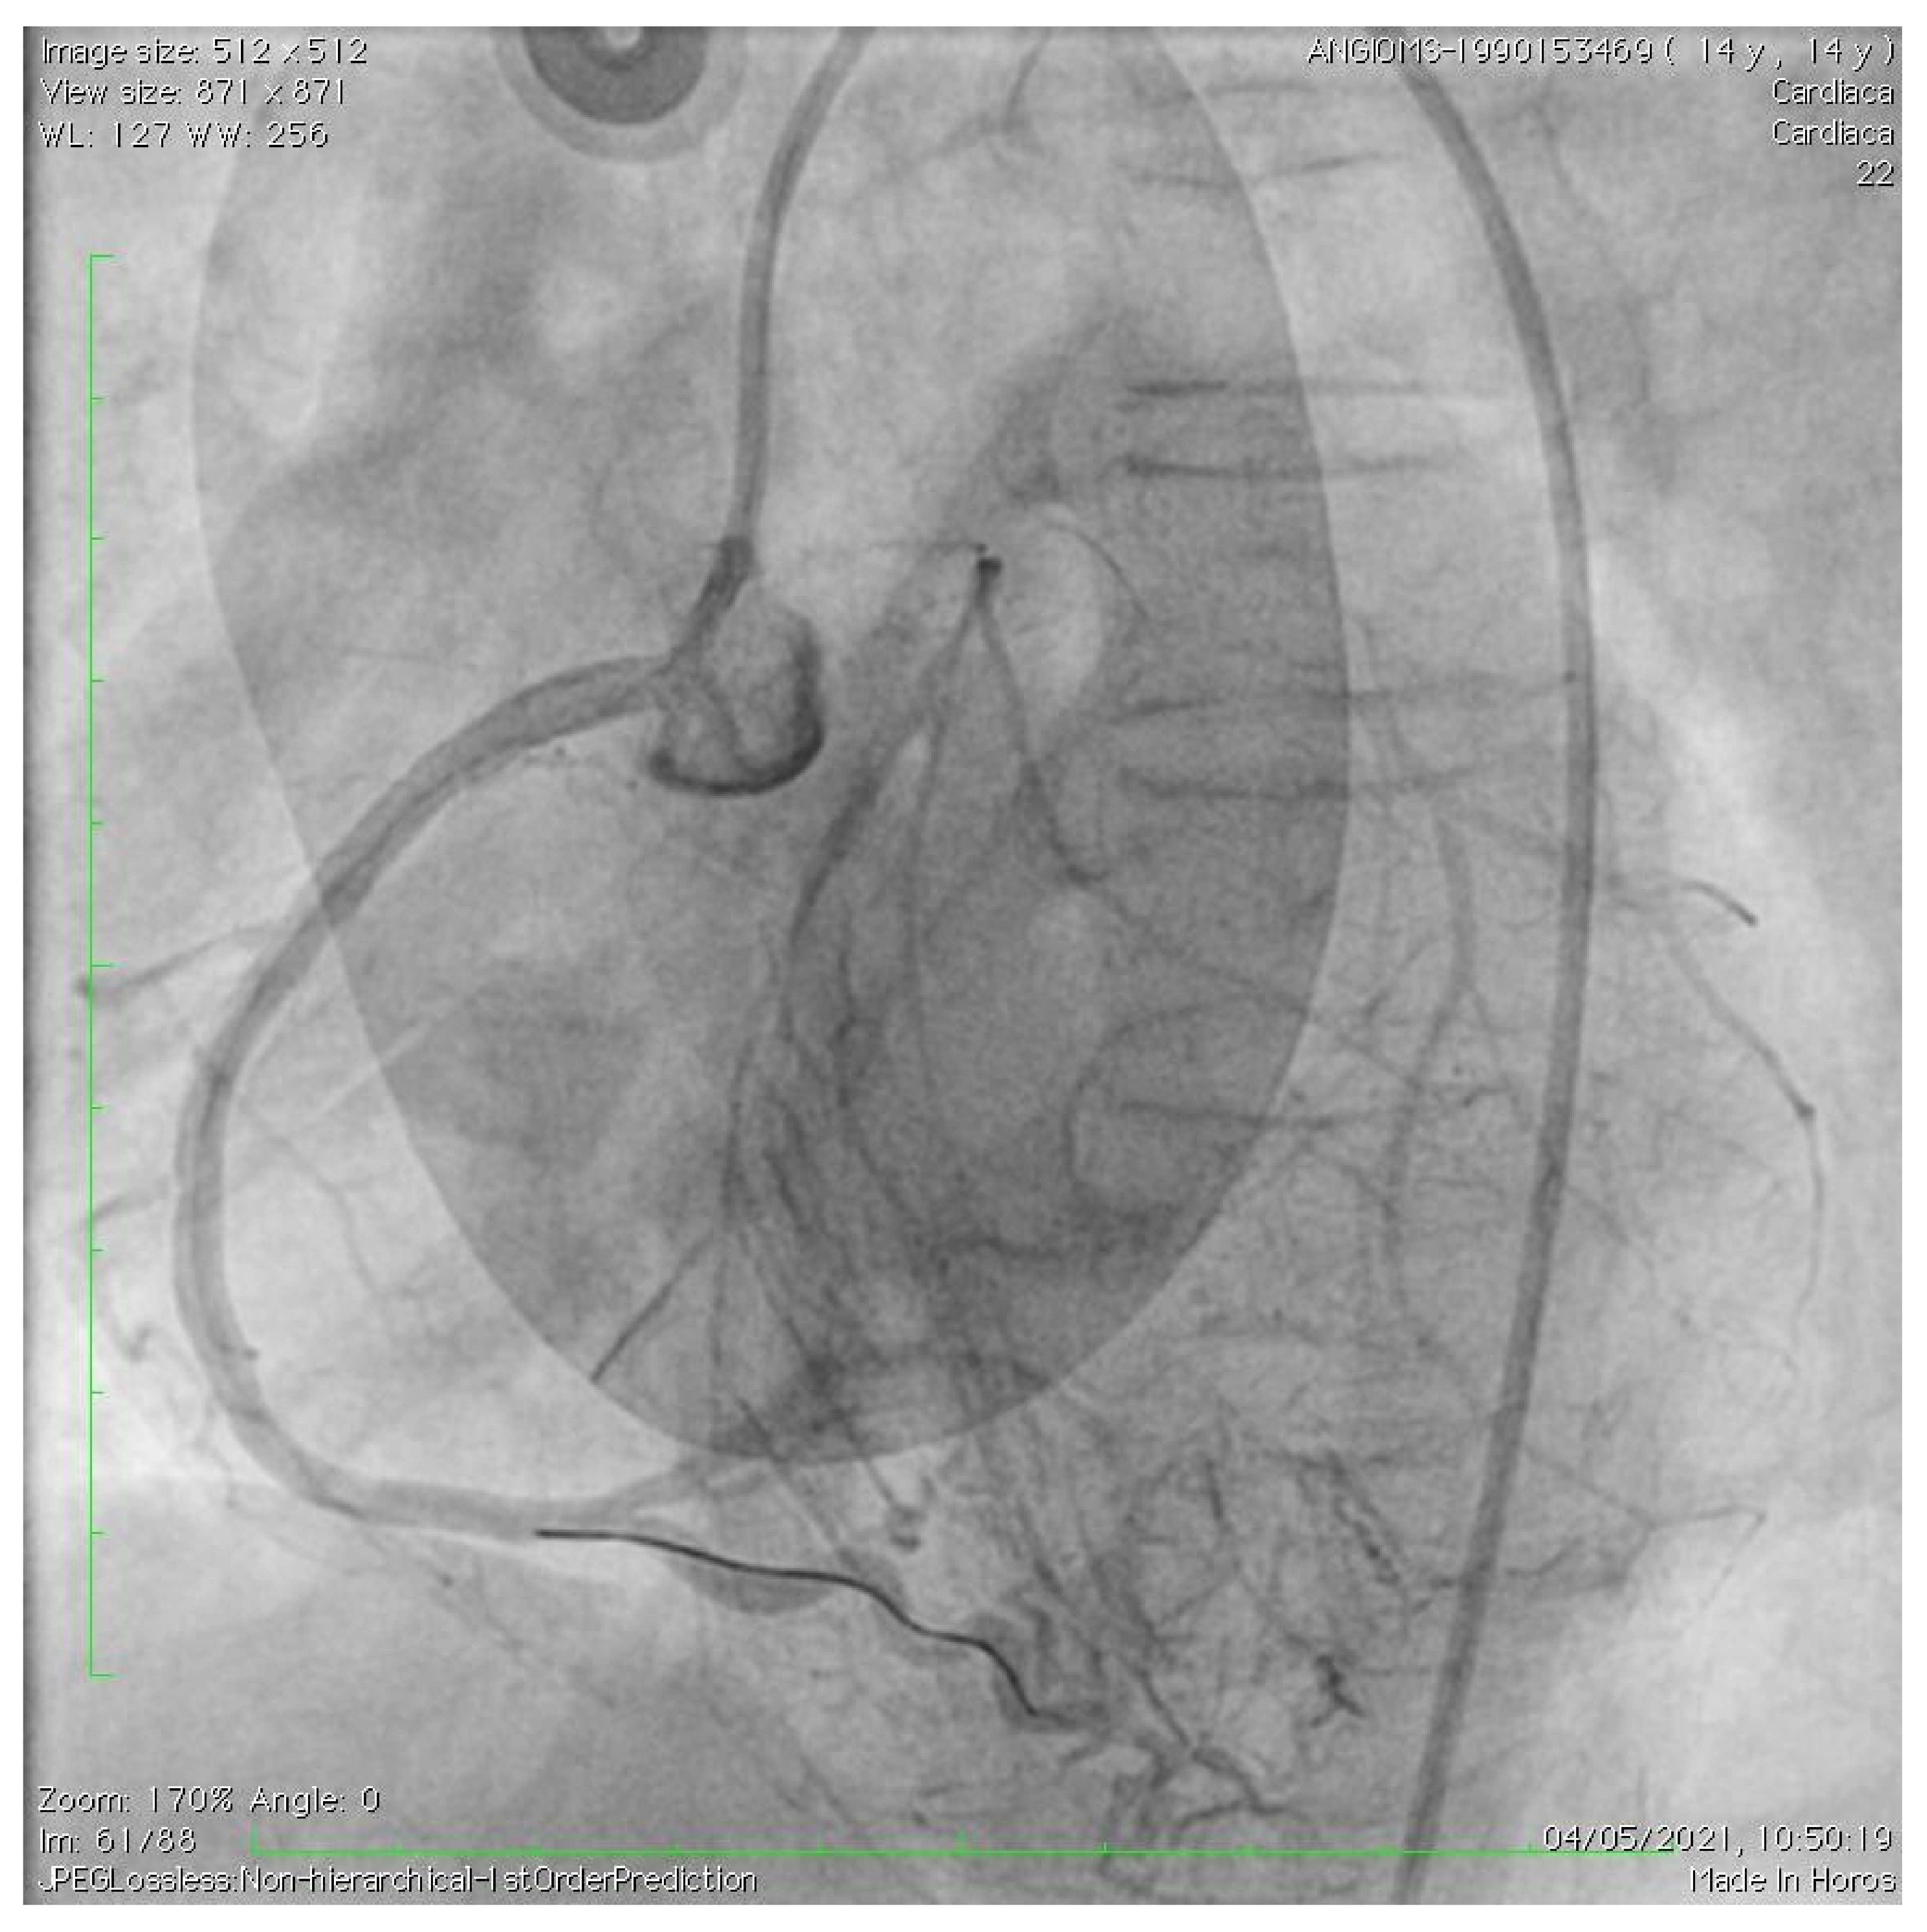

Acute Coronary Syndrome Treated with Percutaneous Coronary Intervention in Hutchinson–Gilford Progeria

2. Case Description

De Simone, L.; Chiellino, S.; Spaziani, G.; Porcedda, G.; Calabri, G.B.; Berti, S.; Favilli, S.; Stefani, L.; Santoro, G. Acute Coronary Syndrome Treated with Percutaneous Coronary Intervention in Hutchinson–Gilford Progeria. Children 2023, 10, 526. https://doi.org/10.3390/children10030526